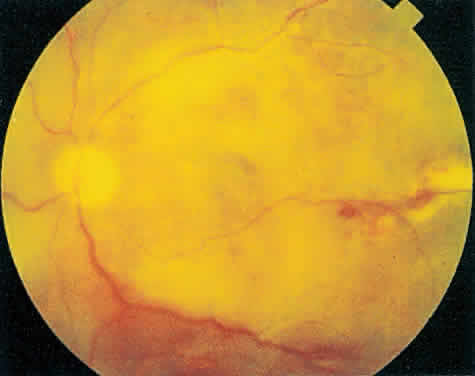

The hallmark lesion of CMV retinitis is a necrotizing, full-thickness retinitis that results in retinal cell destruction. CMV often initially affects retinal tissue adjacent to major retinal blood vessels or the optic disc (Fig. 1). This is consistent with the concept that the virus is spread to the retina hematogenously. In most cases, the pattern of infection is classic and distinctive, making clinical diagnosis straightforward. The area of active retinitis has a granular, dirty-white appearance. As the virus attacks the endothelial cells of blood vessels, hemorrhage is common. Advancement in the retinitis by both direct cell-to-cell transmission as well as spread by way of adjacent satellite lesions can be seen. Except for cases in which retinitis is acute, it is common to see areas of healed retinitis beside areas of active necrosis. Areas of burned-out necrosis show absence of any retinal tissue, whereas the underlying retinal pigment epithelium assumes a “salt and pepper” appearance. CMV retinitis can present initially as either large areas of retinal necrosis with hemorrhage or one or more small, focal areas of retinal whitening.1,12,14 These small, focal lesions may on occasion be confused with cotton-wool spots or lesions of toxoplasmosis.5,27 Unlike cotton-wool spots, focal areas of CMV may appear outside the posterior pole. These early, focal infiltrates of CMV may not be associated with retinal hemorrhages or vitreous cells.

Fig. 1. Typical appearance of peripapillary cytomegalovirus retinitis with hemorrhage and exudate. Despite the proximity to the optic nerve, the visual acuity was 20/20 (6/6) and the patient had no symptoms.